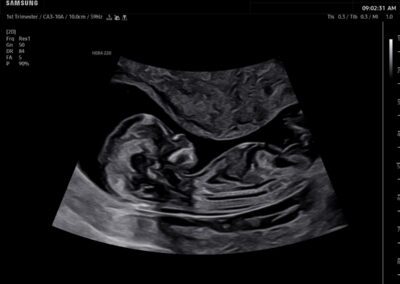

In-depth evaluation of maternal and fetal conditions requiring specialized care such as diabetes, hypertension, thyroid disease, autoimmune disorders, or fetal growth or anatomy concerns.

Comprehensive, advanced and expert MFM care for high-risk pregnancies